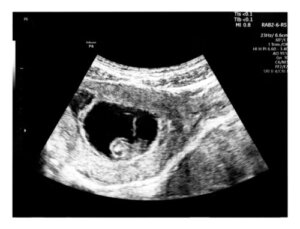

In questo sonogramma è possibile osservare la presenza dell’embrione e valutare lo stato di salute dei tessuti materni. Inoltre, con questa ecografia vengono valutati i seguenti parametri:

- Il corretto impianto dell’embrione all’interno dell’endometrio (cioè la parete interna dell’utero). Vengono determinati il sito di localizzazione e le dimensioni della vescicola gestazionale, nota anche come sacco gestazionale.

- Il sacco gestazionale. Questa è una piccola sfera scura, con un bordo chiaro, che misura circa 8 millimetri in questo momento. Tra le sue funzioni più importanti spicca l’apporto dei nutrienti necessari all’embrione durante le prime settimane. All’interno di questa struttura si trovano la cavità amniotica, il sacco vitellino e il futuro bambino.

- L’embrione. Sebbene sia ancora troppo piccolo per essere visualizzato in dettaglio, è visto come un ispessimento della parete del sacco gestazionale, vicino al sacco vitellino. Nel caso in cui non sia possibile oggettivare in quel momento, lo specialista ordinerà una nuova ecografia 2 settimane dopo.